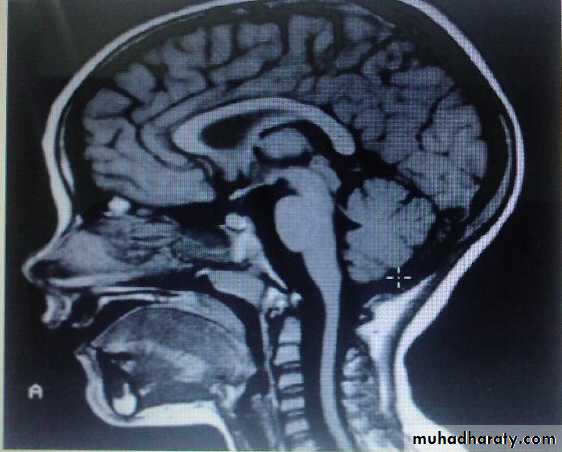

Group of heterogeneous inherited disorders characterized by slowly progressive cerebellar ataxia that affects gait early and severely and may eventually confine the patient to bed. They show considerable clinical variability .Most of them begin in adulthood. Atrophy of the cerebellum and sometimes also of the brainstem may be apparent on CT or MRI scans. Definitive diagnosis is by genetic testing. Treatment is symptomatic.Fridrich Ataxia

Investigation:1- MRI brain and spine.

develop in chronic alcoholics lasting 10 or more years, probably as a result of associated nutritional deficiency. most common in men. usually start between 40 and 60 years.Degenerative changes are largely restricted to the superior vermis, usually insidious in onset & gradually progressive over weeks to months eventually reaching a stable level of deficit, Gait ataxia is a universal feature, heel-knee-shin test is +ve in about 80%. CT scan or MRI may show cerebellar atrophy. No specific treatment is available. Abstinence from alcohol, combined with adequate nutrition, leads to stabilization in most cases. All patients with this diagnosis should receive thiamine to prevent development of Wernicke encephalopathy.

1-Brain MRI